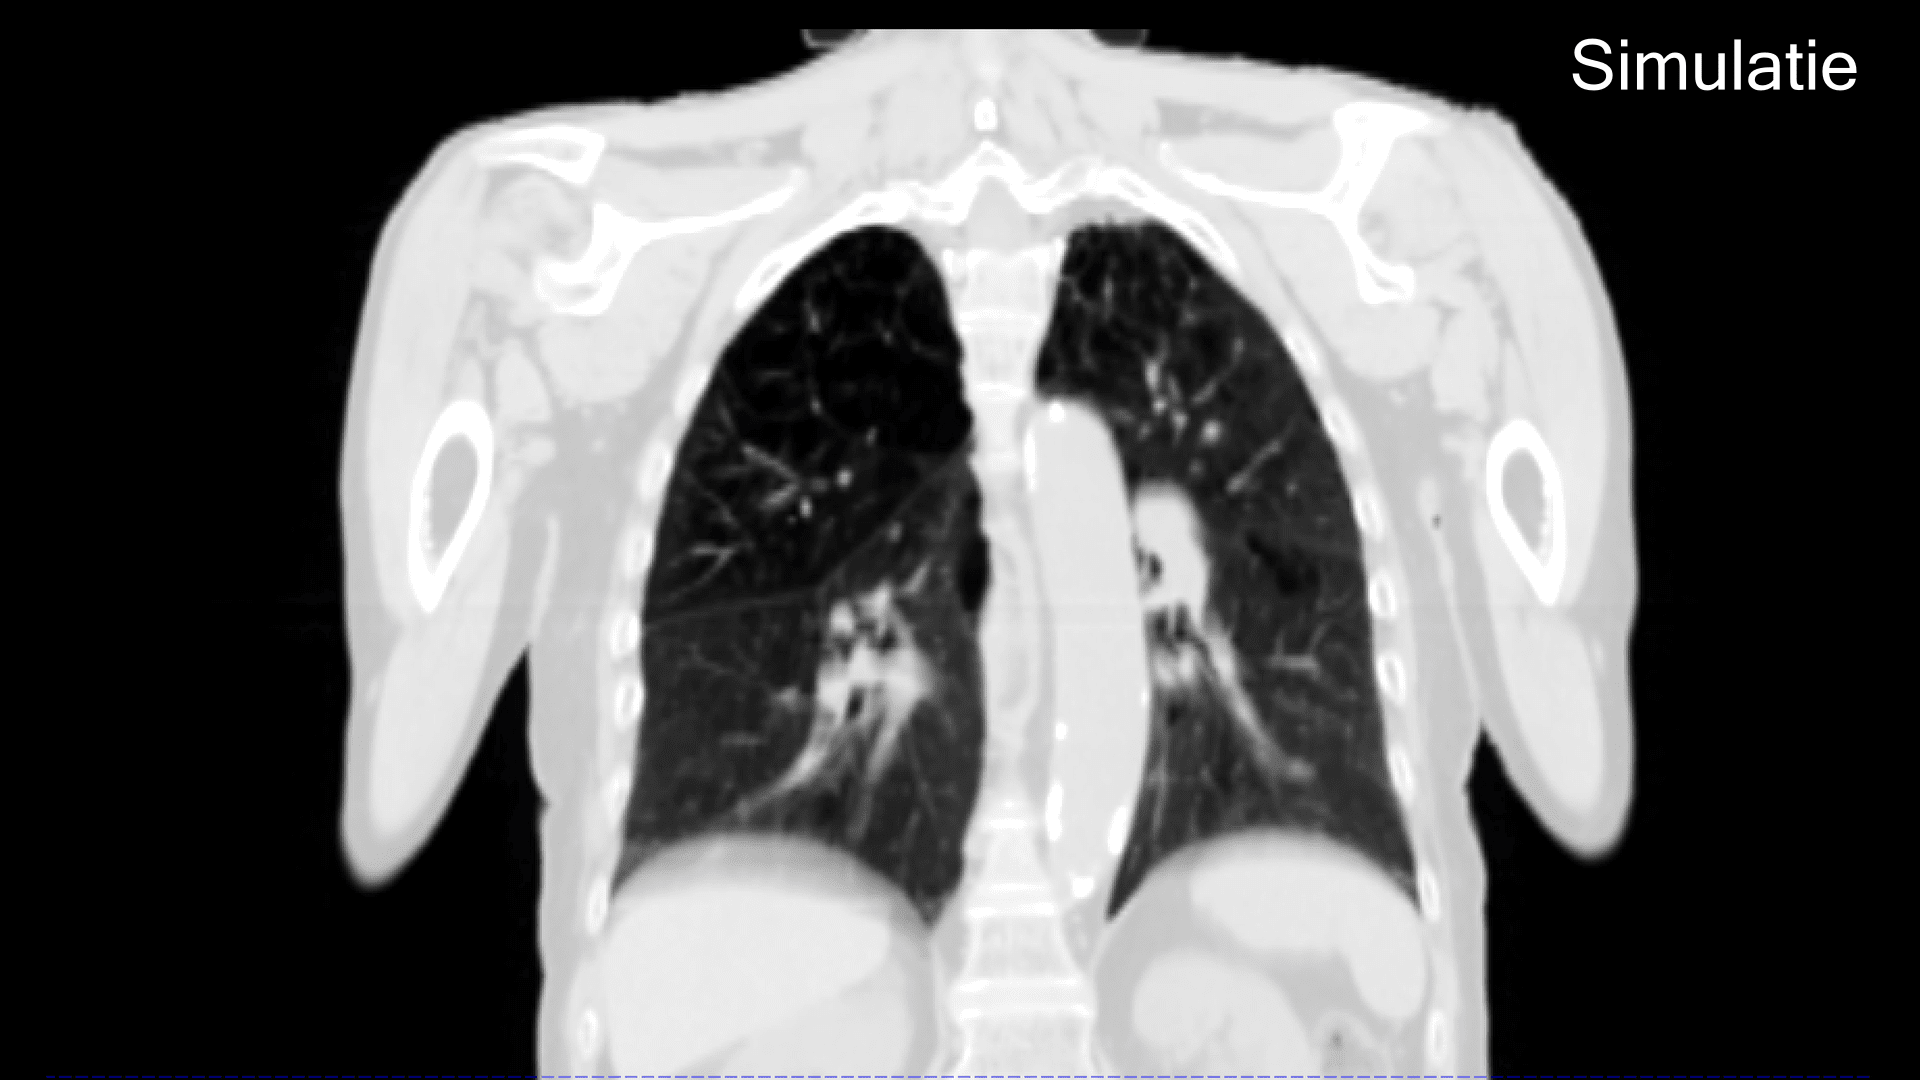

Voor elke bestraling wordt er een controle scan gemaakt. Hiermee kunnen we heel nauwkeurig de positie van het doelgebied en jouw omliggende organen bepalen.

De scan die we voor elke bestraling maken, vergelijken we met de scan van de simulatie. We leggen de scans over elkaar waarmee we zorgen dat de straling op exact de goede plek komt.